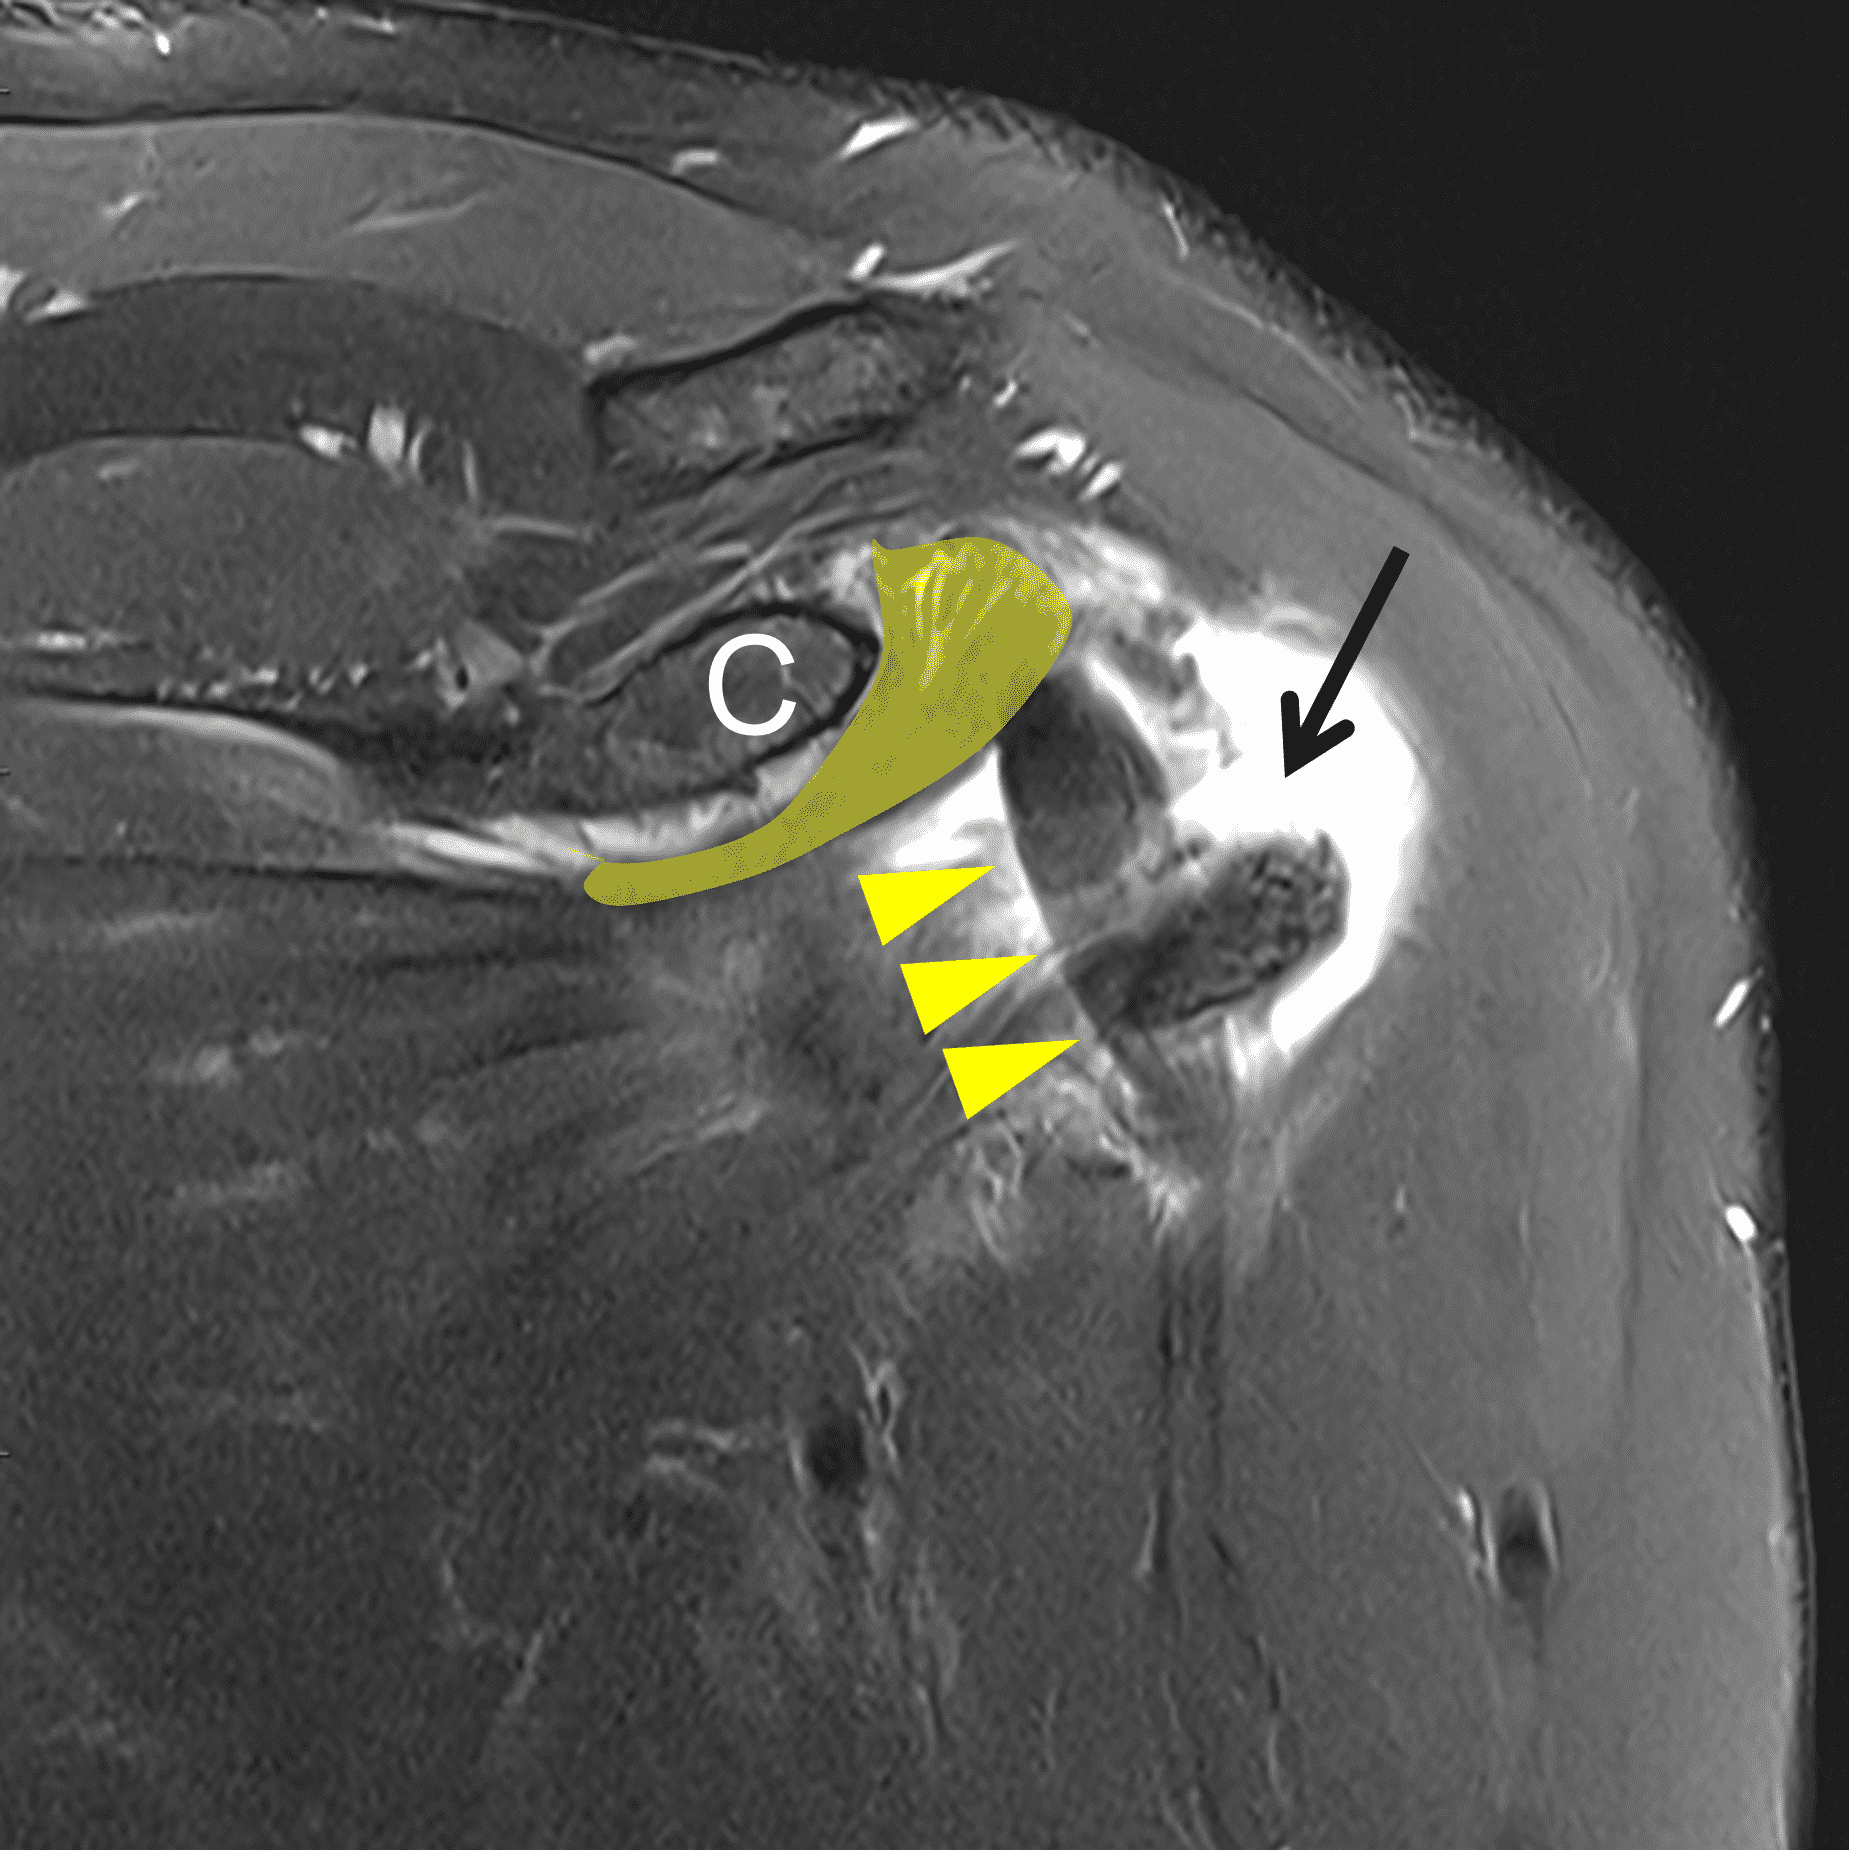

Figure 2: (2A) Axial image demonstrates a torn and retracted subscapularis tendon (solid arrow), empty bicipital groove (dotted arrow), and tendinosis of the medially dislocated long head biceps tendon (arrowhead). (2B) Oblique coronal image shows a fluid filled gap at the superior subscapularis tendon insertion (arrow), medially dislocated biceps tendon (arrowheads), and the comma sign (shaded) – a vertically-oriented curved band of soft tissue that partly wraps around the coracoid (C). The ‘comma’ is composed of the detached superior glenohumeral ligament, coracohumeral ligament, and medially retracted superolateral subscapularis. (2C) Oblique sagittal image shows the torn, retracted superior subscapularis tendon (shaded) displaced superomedially within the rotator interval.

The comma sign (Figure 3) is a well-known arthroscopic finding initially described in 2003 by Lo and Burkhart.14 The sign is less well known amongst radiologists but can be accurately identified on pre-operative MR imaging.2,15 The comma sign serves as a surgical indicator of a full-thickness, retracted subscapularis tear. The tissue that comprises the comma sign is composed of the torn insertional fibers of the superior subscapularis, which is separated from the more caudal fibers and superiorly and medially displaced together with the superior glenohumeral ligament, and coracohumeral ligament. The torn fibers are pulled superiorly and cranially by a concomitant retracted supraspinatus tear.2 The concavity of the comma should be the coracoid process of the scapula (Figures 2 and 3).